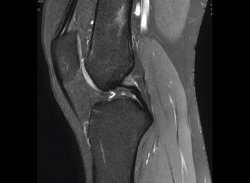

1.2.2. Ligamento cruzado anterior (LCA) (Figuras 40, 41, 42, 43 y 44)

Figura 40. Corte de secuencia sagital T2 Fat-Sat de resonancia magnética de rodilla: ligamento cruzado anterior normal.

Figura 41. Cortes de secuencia sagital T2 Fat-Sat de resonancia magnética de rodilla: rotura central del ligamento cruzado anterior.

Figura 43. Corte sagital oblicuo T2 de resonancia magnética de rodilla: plastia del ligamento cruzado anterior íntegra.

Figura 44. Corte de secuencia sagital T2 Fat-Sat y T2 de resonancia magnética de rodilla: rotura de plastia del LCA.